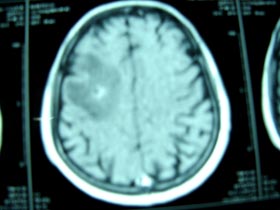

- Đặc biệt chụp cắt lớp vi tính ở não cho thấy có 6 ổ khối u nhỏ ở 2 bên bán cầu não, kích thước nhỏ 20mm, khối u tròn, không có chân, bên trong có hoại tử trắng đều trên film.

+ Chụp cắt lớp vi tính ở não:

·Các khối u đã thoái triển chỉ còn lại 1-2 khối u nhỏ, kích thước 10-15mm, bên trong đã hoại tử trắng, không có chân, không có phù nề xung quanh khối u.

·Không có hình ảnh bất thường ở 2 bán cầu não.

| Hình 2. Hình ảnh chụp vi tính cắt lớp não trước khi điều trị |